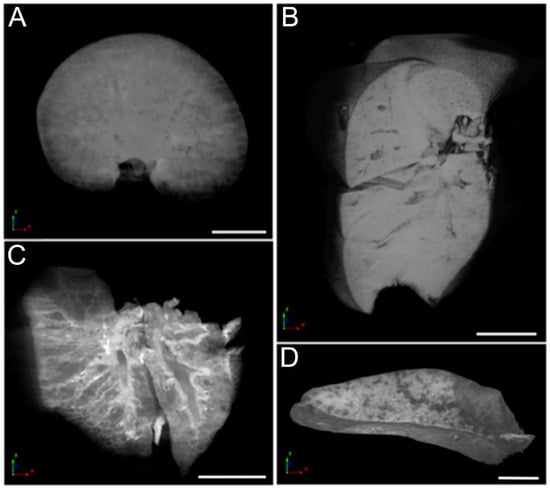

2.7. Organ Micro-Computed Tomography (Micro-CT) and Histological Analysis

3.6. Micro-CT Analysis